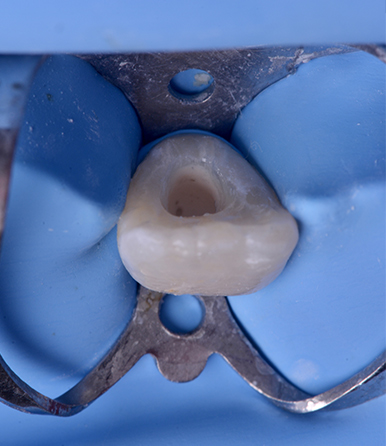

Fig. 01 : la situation initiale.

À l’examen clinique la couronne dentaire est intacte, l’examen des tissus parodontaux met en évidence la présence d’une fistule vestibulaire.

Une patiente âgée de 12 ans est adressée au cabinet pour la réalisation du traitement endodontique de la 21. L’interrogatoire médical ne révèle aucun problème de santé général, la patiente rapporte un antécédent de traumatisme, des antécédents de douleur et de tuméfaction.